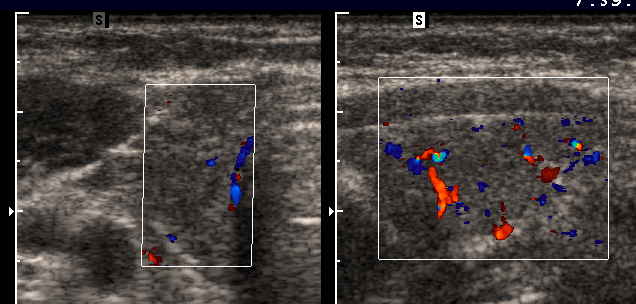

Mit

der Ultraschalluntersuchung der

Schilddrüse kann der erfahrene Untersucher

schnell und einfach Größe, Struktur und

Lage der Schilddrüse beurteilen. Vorhandene

Knoten können nach Aussehen, Struktur und

Durchblutung eingeteilt werden. Zusammen mit der

Funktionslage und eventuell erforderlichen weiteren

Charakteristik:

|

echoarme

Schilddrüse

Farbduplex

gesteigerte

Durchblutung

Diagnose:

M.

Basedow